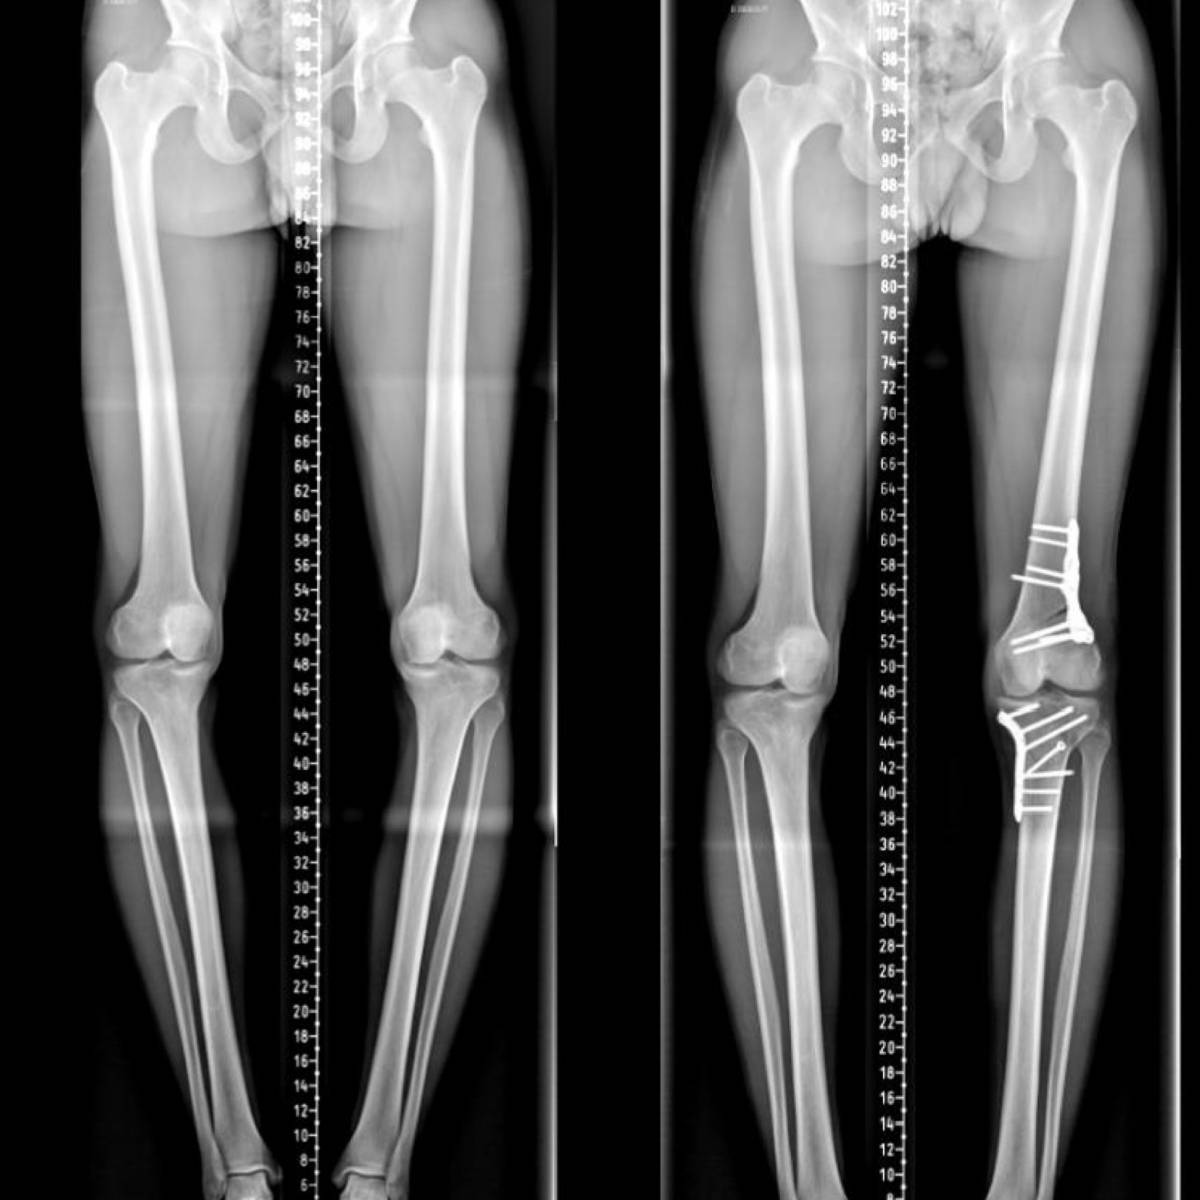

ostéotomie bifocale vue frontale ostéotomie bifocale vue frontale

Révolutionner l'Ostéotomie du Genou : Le Leadership de l'Institut du Mouvement et de l'Appareil Locomoteur

Découvrez comment l'Institut du Mouvement et de l'Appareil Locomoteur redéfinit les standards en ostéotomie autour du genou, affirmant son rôle de leader mondial grâce à une performance clinique exceptionnelle, une contribution scientifique de premier plan, et une reconnaissance internationale incontestée